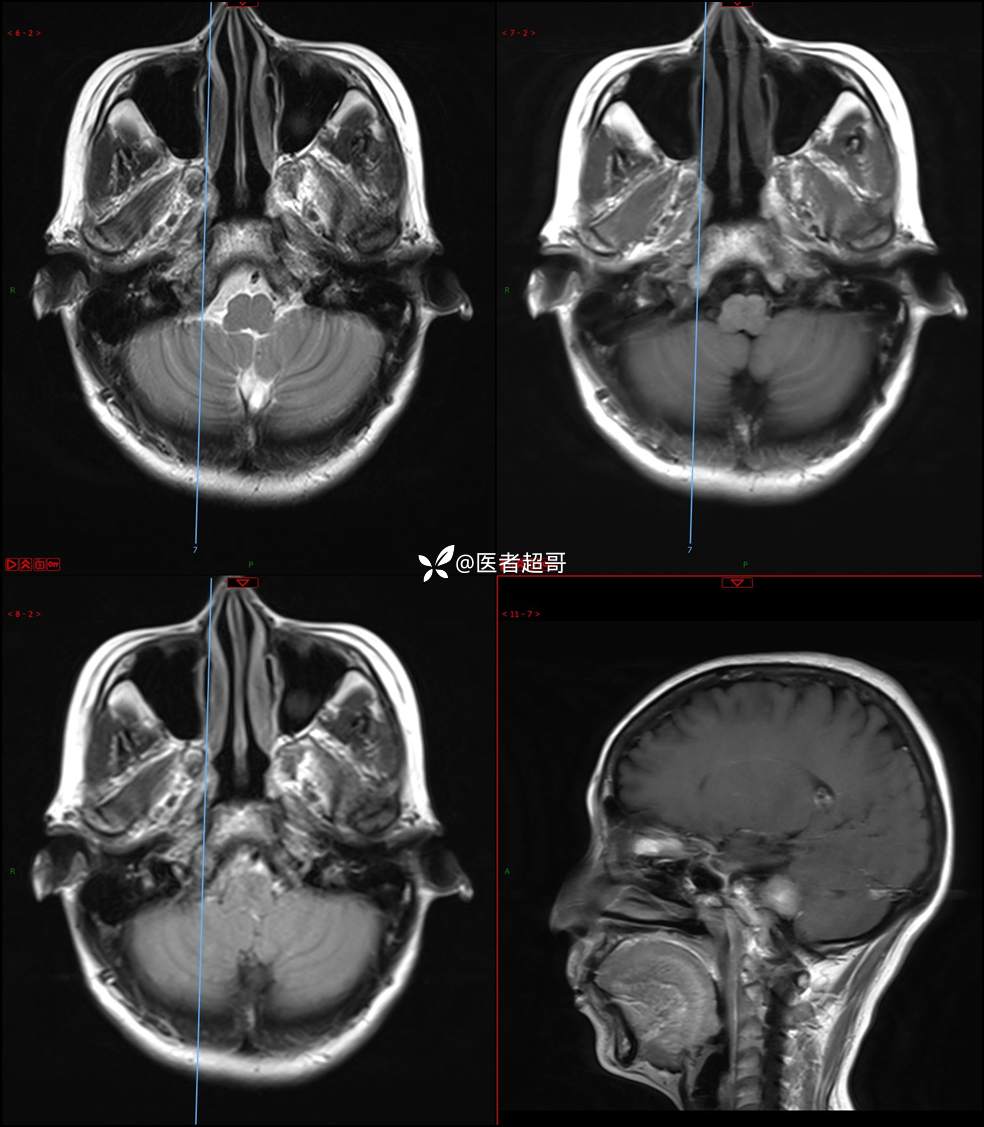

CPA区占位,是鞘瘤?脑膜瘤?请赏析!

主 诉:耳鸣3年,头晕伴恶心4天。

现病史:患者3年前出现耳鸣,蝉鸣音,反复发作,夜间自觉明显,于2018年8月至我院耳鼻喉科就诊,行颅脑CT检查未发现明显异常改变,给予对症处理(具体不详);4天前突发头晕,伴明显恶心,至市人民医院就诊,行颅脑CT未见明显异常,颅脑MRI发现右侧桥脑小脑角区占位性病变。本次发病来无明显头痛,无肢体抽动,无大小便失禁。为求进一步诊治,遂来我院门诊,以“听神经良性肿瘤”收住入院。发病来,患者神志清,精神可,二便正常,饮食可,睡眠不佳,近期体重无明显变化,否认癫痫发作病史。